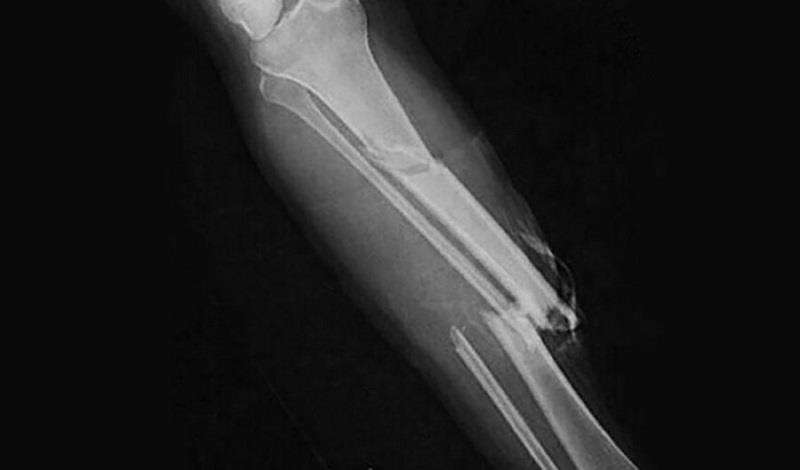

Ладно, к ноге вернуться стоит. Ломать по-настоящему не обязательно. Нужно найти врача и получить от него справку, что лечил герр Барерас открытый перелом во Львове и передвигаться не мог. На вытяжке лежал. Рентгеновский снимок ещё присовокупить, если их уже делают во Львове и главное — нужен шрам на ноге. Ну, раз это открытый перелом, то кость торчала из ноги, порвав кожу и мышцы. Снимок и справка не подтверждение, в НКВД дураков не, а вот в плюс к ним шрам правильный на левой ноге, или лучше на правой. Нет, на левой пусть. Так вот шрам правильной формы и справка и снимок — это почти доказательство.

— Скальпелем, кожу разрезать так, чтобы было похоже на открытый перелом, и потом зашить суровыми нитками, или чем вы там шьёте. Только инструмент прокипятить перед этим и нитку и потом йодом обработать. Шрам должен быть видимым, и чтобы специалист решил, что это именно последствия открытого перелома, — закончил Иван Яковлевич под настораживающее молчание пана Крутицкого младшего.